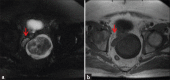

Schwannomas are benign soft-tissue tumors that arise from peripheral nerve sheaths throughout the body and are commonly encountered in patients with neurofibromatosis Type 2. The vast majority of schwannomas are benign, with rare cases of malignant transformation reported. In this pictorial review, we discuss the magnetic resonance imaging (MRI) appearance of schwannomas by demonstrating a collection of tumors from different parts of the body that exhibit similar MRI characteristics. We review strategies to distinguish schwannomas from malignant soft-tissue tumors while exploring the anatomic and histologic origins of these tumors to discuss how this correlates with their imaging findings. Familiarity with the MRI appearance of schwannomas can help aid in the differential diagnosis of soft-tissue masses, especially in unexpected locations.